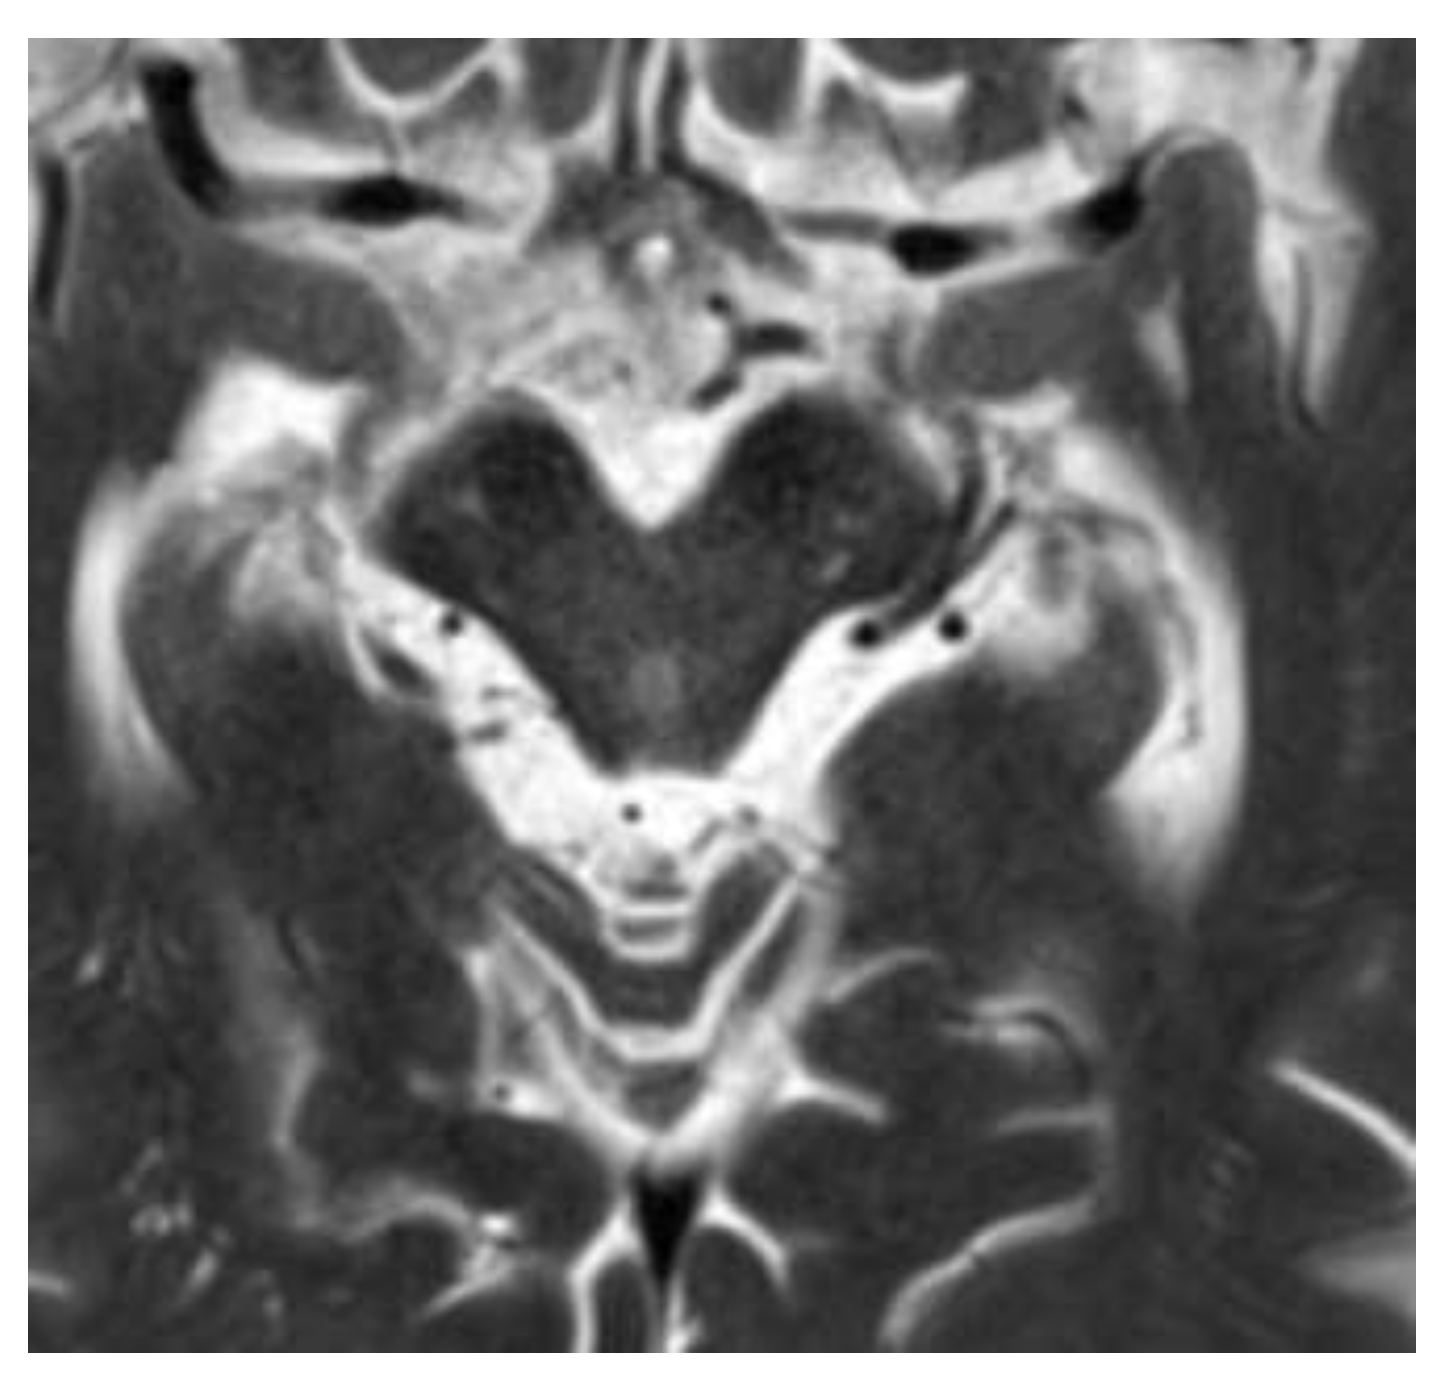

- Hummingbird sign. In midbrain atrophy, the thinning of the midbrain tegmentum and the widening of the superior cerebellar peduncles contribute to this distinctive imaging pattern. The superior cerebellar peduncles extend upward, and when combined with the atrophy of the midbrain, they create a silhouette reminiscent of a hummingbird (Figure 1) [25].